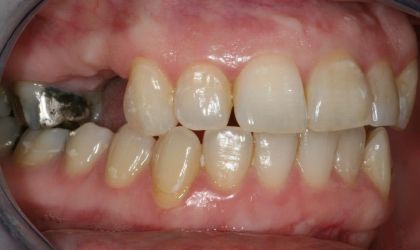

Before

After